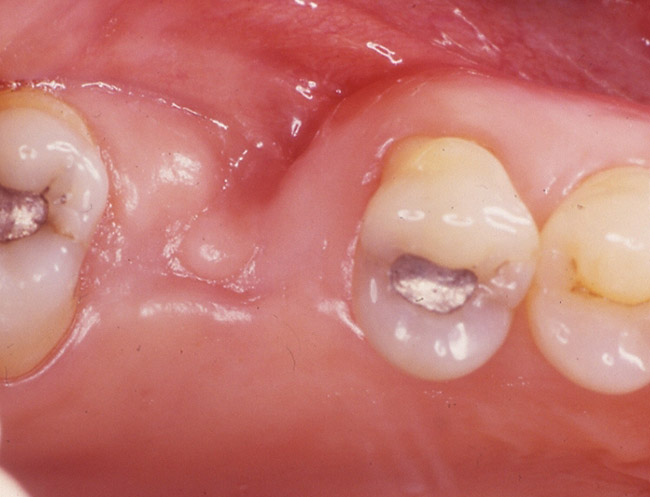

Case 2: Extraction with Socket Preservation

The patient was a 65-year-old healthy man who was referred for a periodontal evaluation of tooth No. 28. The patient presented with the chief complaint of pain and swelling in the lower right side of his mandible. Clinical examination revealed deep probing depth primarily (9 mm) on the distal-facial aspect of tooth No. 28. The tooth presented with grade 2 mobility. A periapical radio­graph of the tooth revealed the presence of a radiolucent appearance that was more significant at the midroot level (Figure 2A). The prognosis was determined to be "hopeless" because of a root fracture.

The patient was scheduled for extraction of the tooth, along with socket preservation. After extraction, the socket was curetted. Bone loss on the buccal aspect as a result of infected tissue was noted (Figure 2B). After socket curettage, the socket was grafted using a combination of freeze-dried bone allograft combined with a calcium sulfate bone graft barrier (Figure 2C). The patient was placed on antibiotic and anti-inflammatory medications. Six months after the socket preservation procedure, the site was prepared for implant placement. At the time of implant placement, a core of bone was harvested from the socket preservation site and analyzed histologically (Figure 2D and Figure 2E).